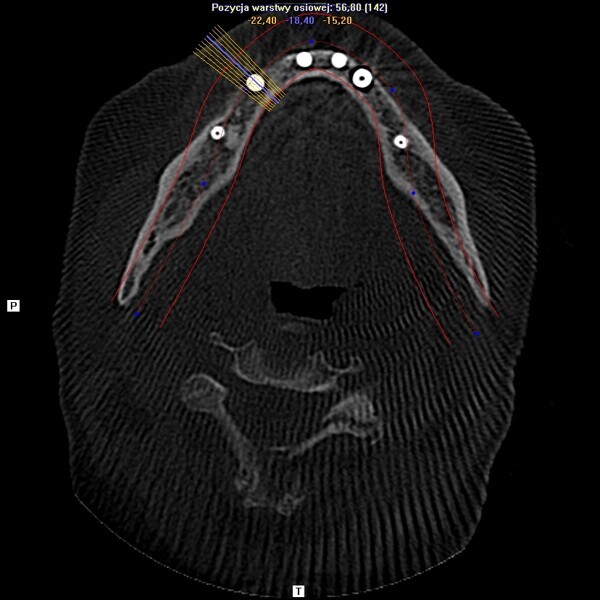

Natychmiastowa implantacja i zaopatrzenie protetyczne pacjentów z zaawansowaną chorobą przyzębia